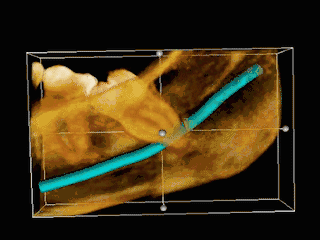

TAC 3D de una muela del juicio impactada adyacente al nervio alveolar inferior antes de la extracción de la muela del juicio. | ||

Si el diente no se puede evaluar únicamente con el examen clínico, el diagnóstico se realiza mediante una radiografía panorámica o una tomografía computarizada de haz cónico. Cuando las muelas del juicio no erupcionadas todavía tienen potencial de erupción, se utilizan varios factores predictivos para determinar la probabilidad de que los dientes se impacten. La relación de espacio entre la longitud de la corona del diente y la cantidad de espacio disponible, el ángulo de los dientes en comparación con los otros dientes son los dos predictores más utilizados, siendo la relación de espacio la más precisa. A pesar de la capacidad de movimiento en la edad adulta temprana, la probabilidad de que el diente se impacte puede predecirse cuando la relación entre el espacio disponible y la longitud de la corona del diente es inferior a 1.:[5] 141

Las complicaciones a largo plazo pueden incluir complicaciones periodontales como la pérdida de hueso en el segundo molar tras la extracción de las muelas del juicio. La pérdida ósea como complicación tras la extracción de las muelas del juicio es poco frecuente en los jóvenes, pero está presente en el 43% de las personas de 25 años o más.[23] La lesión del nervio alveolar inferior que provoca entumecimiento o entumecimiento parcial del labio inferior y la barbilla ha registrado tasas que varían ampliamente del 0,04% al 5%.[23] El estudio más amplio es el de una encuesta de 535 cirujanos orales y maxilofaciales de California, en el que se registró una tasa de 1:2.500.[26]

La coronectomía es un procedimiento en el que se extrae la corona de la muela del juicio impactada, pero las raíces se dejan intencionadamente en su sitio. Está indicada cuando no hay enfermedad de la pulpa dental ni infección alrededor de la corona del diente, y existe un alto riesgo de lesión del nervio alveolar inferior.[32]